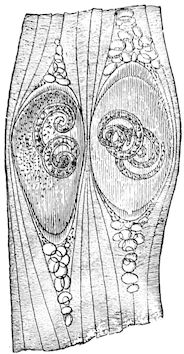

Fig. 8.—Transverse section through the middle region of the face in a pig suffering from osseous cachexia.

18In the final stages, the bones may be cut with a knife, and a time arrives when bony tissue seems completely to have disappeared; thus, as shown in Fig. 8 herewith, it was possible to cut the entire head of a pig into thin slices without the slightest difficulty. All parts of the head had been affected by the softening change.

From the chemical point of view, the diminution in mineral salts and in phosphate of calcium has long been recognised, but the degree of this change varies according to the phase. In human beings the proportions have been estimated as follows: Normal bone, 50 to 80 per cent. of phosphate of calcium; bone in persons suffering from osteomalacia, 5 to 20 per cent. of phosphate of calcium. The changes in the ossein have not been carefully studied. We only know that histologically the ossein becomes fibrillar, and that chemically it no longer retains its normal composition.

114. The fourth phase, or period of osteomalacia, i.e. softening of the bones, is also the last. It is rarely seen in large animals like horses and oxen, because accidents so often accompany the preceding stages and necessitate slaughter; but it is common in goats and pigs.

In this phase the bones become elastic, soft and depressible, yielding to the pressure of the operator’s fingers.

Fig. 4.—Deformity of the face in the horse shown in Fig. 2.

The flat bones are particularly liable to this change, which is common to domesticated animals. The bones of the head are the first to suffer; later those of the pelvis. The lower jaw becomes swollen, particularly about the centre of the branches which may attain three, four, or five times, their normal thickness.

The depression in the submaxillary space disappears. The upper jaw undergoes similar changes, becoming deformed and thickened until the cavities of the sinuses and the hollow appearance of the palate are lost, while the face is so changed that it cannot be recognised as that of a horse, goat, etc.

The molar teeth are almost buried, their tables alone being visible at the bottom of a depression, the edges of which rise above the neighbouring parts (pig).

Mastication is clearly impossible, the jaws appear paralysed, the muscles powerless, and only swallowing is possible, a fact which explains why life is only prolonged to this stage in animals which can be fed with a spoon or bottle (pigs and goats). The bones of the cranium, although greatly changed in texture, are always less deformed than those of the face.

The changes are such that it is often easy with a mere post-mortem knife to cut the head completely in two. Osseous tissue, properly so-called, has disappeared.

All the constituent tissues, with the exception of the skin and muscles, i.e., the bone, periosteum and aponeuroses, have the appearance and consistence on section of the fibro-lardaceous tissue seen in chronic inflammation.